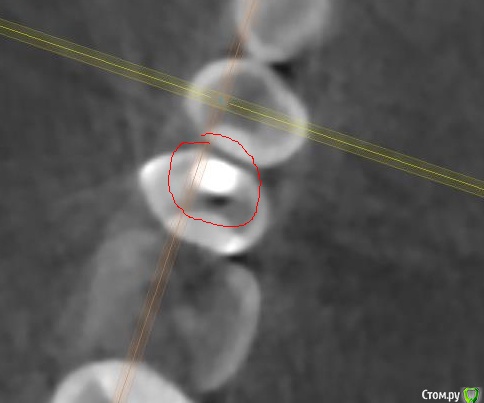

Faramir Опубликовано 30 апреля, 2019 Поделиться Опубликовано 30 апреля, 2019 (изменено) Посетил клинику в которой врач (причем главный) диагностировал кариес между 1.5 со стороны 1.4. На зубе уже была другая пломба со стороны 1.6. Через несколько месяцев я сделал КТ для консультаций по имплантации и рассматривая этот зуб заметил что под пломбой видна не маленькая полость. Обратился в клинику к врачу, после чего мне был вынесен вердикт что это "рог пульпы" и вроде как все нормально. Вопрос может ли быть рог пульпы в 1.5 зубе так высоко и прилегать непосредственно к пломбе черным пятном? Или это банальная ошибка врача который не достаточно утрамбовал материал или материал был не достаточно текуч для заполнения всей просверленной полости? Зуб слегка поднывает иногда. Во что может вылиться если зуб оставить как есть или его нужно обязательно переделать? Фото с КТ прилагаю. Изменено 30 апреля, 2019 пользователем Faramir Ссылка на комментарий